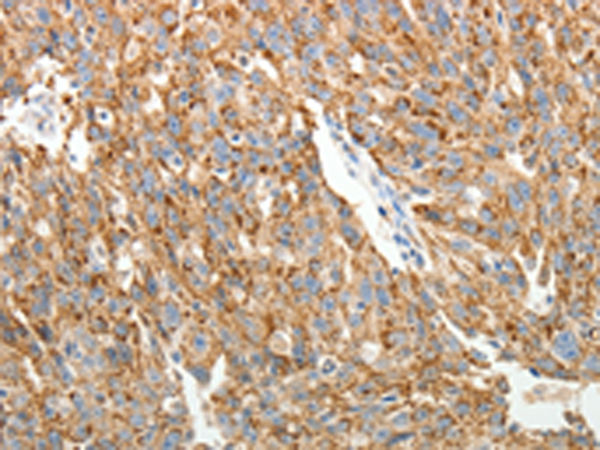

分类: 科研抗体货号: P11132别名: MAP-2; Mtap2; Mtap-2应用: IHC反应种属: Human, Mouse, Rat